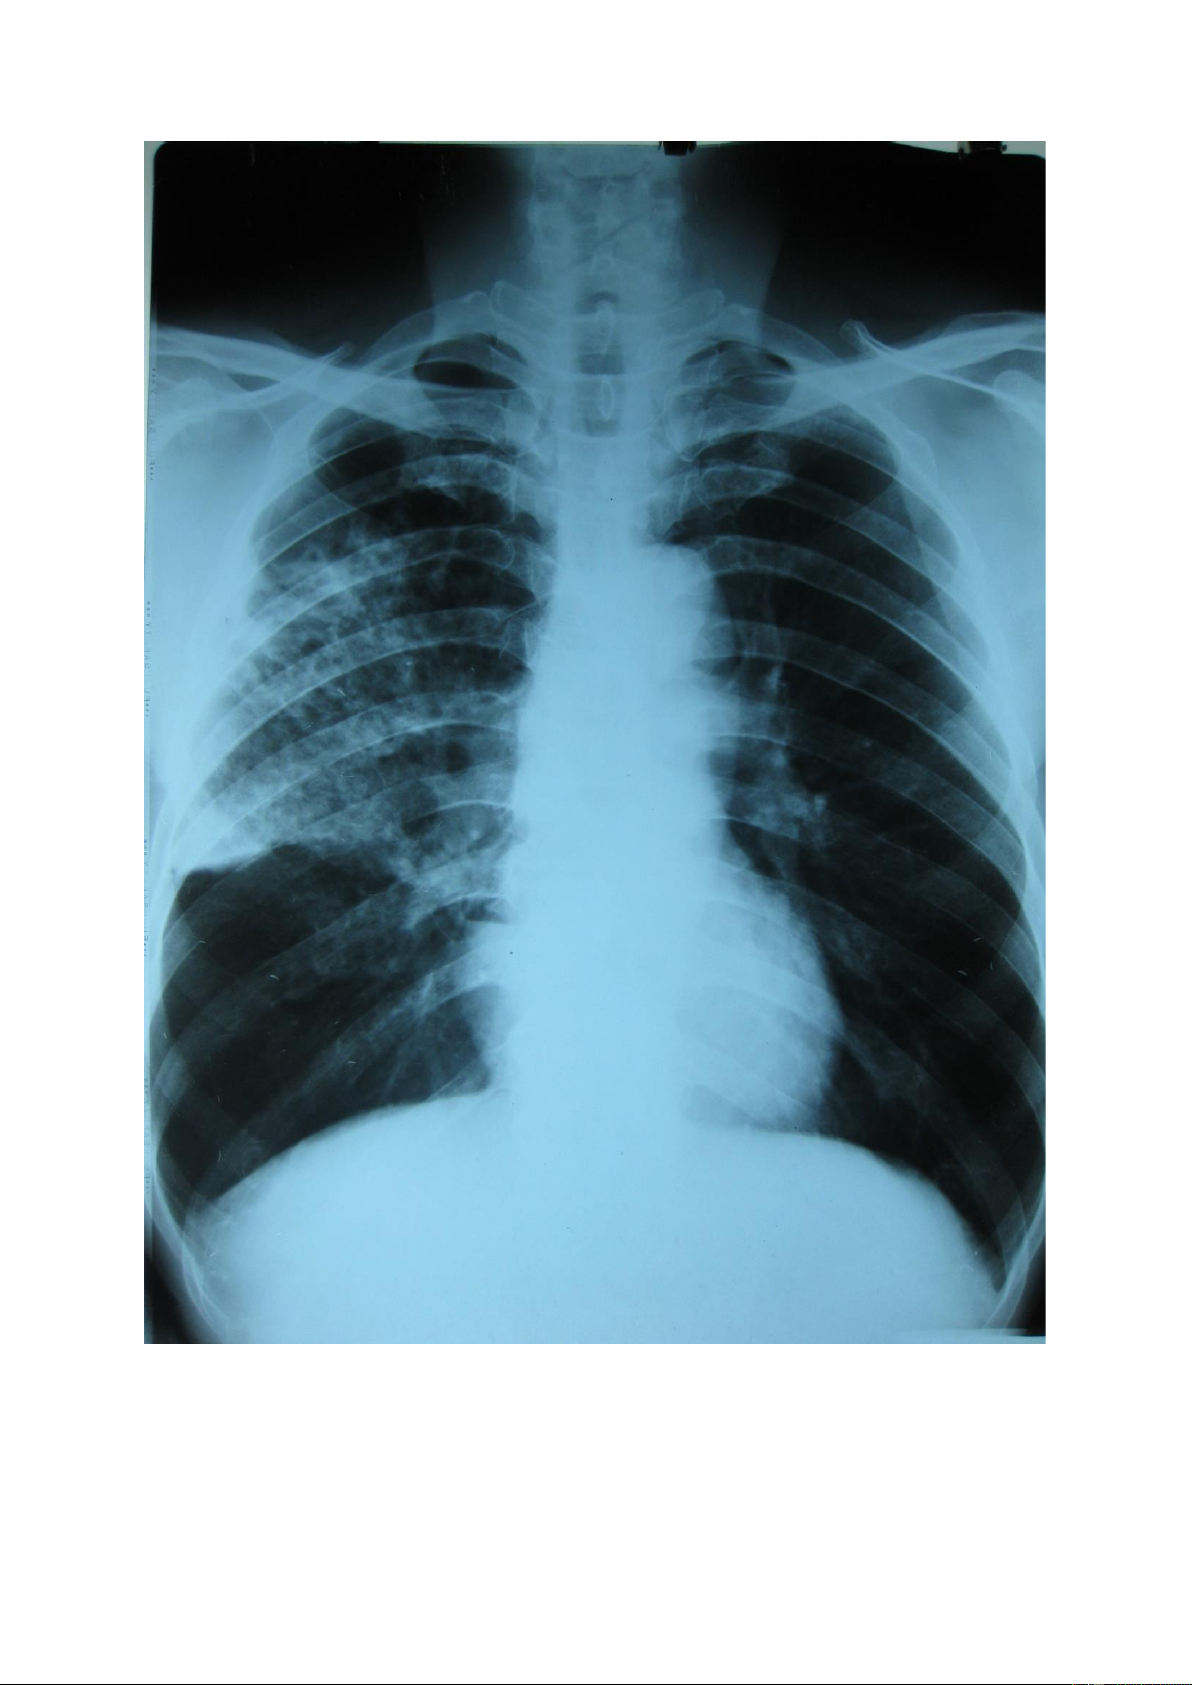

Dải mờ - dải xơ: dải mờ là tổn thương mờ tạo thành một hoặc nhiều vệt (màu

trắng) dài ngắn khác nhau, dải xơ thường là di chứng để lại của dải mờ khi hồi phục

nên đậm độ cản quang cao hơn dải mờ. lOMoAR cPSD| 22014077 lOMoAR cPSD| 22014077 1.6.